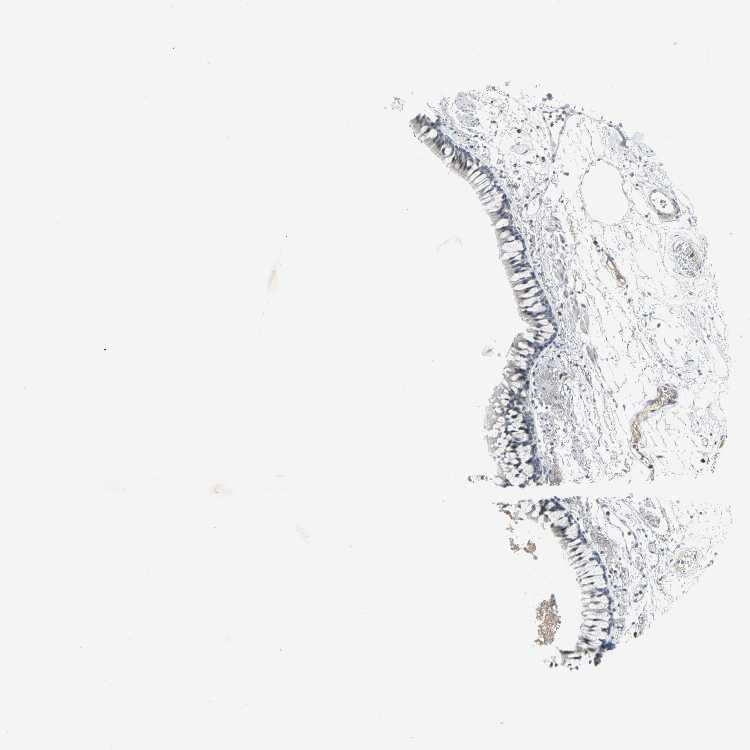

TISSUE PRIMARY DATA BRONCHUS Show tissue menu

Bronchus

BRONCHUS - Antibody stainingi

Antibody staining in the annotated cell types in the current human tissue is reported as not detected, low, medium, or high, based on conventional immunohistochemistry profiling in selected tissues. This score is based on the combination of the staining intensity and fraction of stained cells.

Each image is clickable and will lead to virtual microscopy that enables deeper exploration of all samples and also displays staining intensity scores, fraction scores and subcellular localization as well as patient and tissue information for each sample.

Antibody HPA004098

Respiratory epithelial cells Low